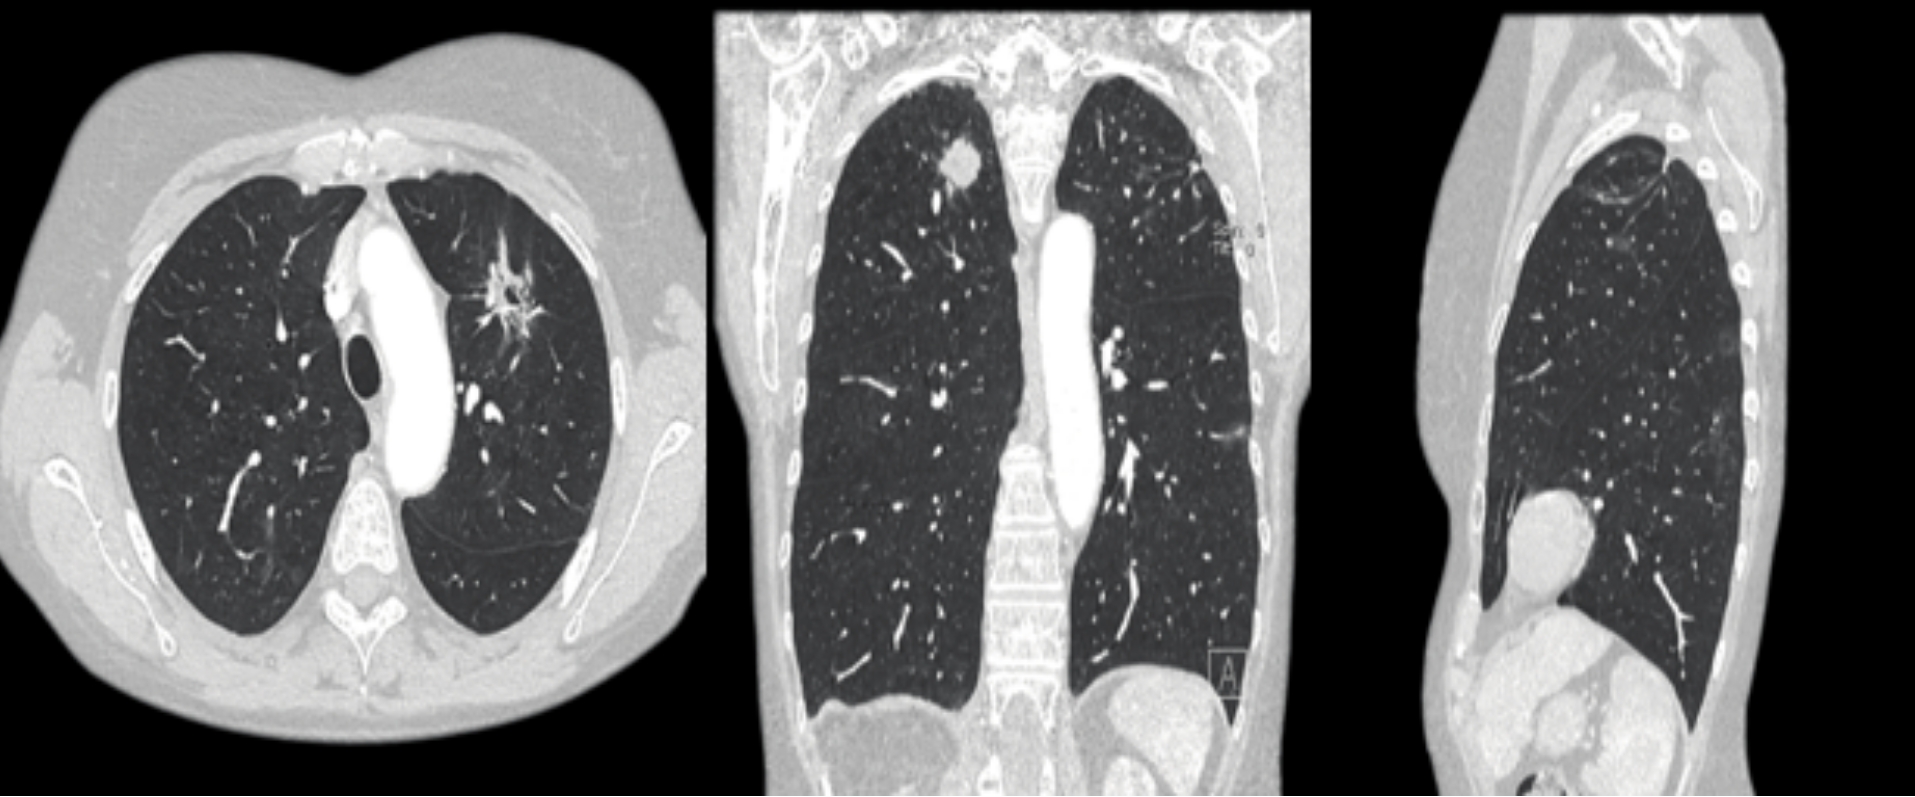

本次引進(jìn)的全新64排128層人工智能螺旋CT具有檢查更加精細(xì)、圖像更加清晰、掃描速度快和輻射劑量小等多種優(yōu)點(diǎn)。除了可進(jìn)行常規(guī)CT檢查、普通增強(qiáng)CT檢查外,還可對(duì)全身大血管、腦血管、心臟血管進(jìn)行檢查;強(qiáng)大的三維重建功能可發(fā)現(xiàn)普通DR、常規(guī)CT所難確診的病變。

該設(shè)備擁有單圈0.33秒/360°的極速掃描,超越之前所有多排螺旋CT,尤其適合心血管成像。胸部成像只需要3秒,全身成像9秒就可完成。

低電壓、低輻射劑量、低對(duì)比劑總量、低對(duì)比劑流速、低對(duì)比劑濃度。該設(shè)備可在不降低圖像質(zhì)量的情況下,提高患者的安全性。特別適用于體檢篩查(如肺結(jié)節(jié)篩查)、兒童檢查(配備兒童專用掃描方案)等。用該設(shè)備做超低劑量肺結(jié)節(jié)篩查,輻射劑量可以降低到普通胸部CT的1/10以下。

用該設(shè)備做心血管系統(tǒng)檢查,能得到對(duì)比度極佳的血管圖像。大大提高了診療的精準(zhǔn)度及工作效率,有利于醫(yī)生及早發(fā)現(xiàn)微小病灶。